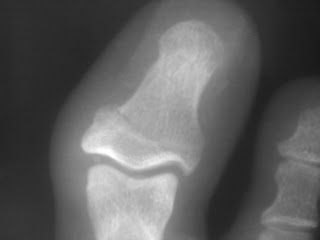

Fractures of the toe are one of the most common lower extremity fractures diagnosed by family physicians. A radiograph, bone scan, and MRI are found in Figures A-C, respectively. Anatomy. WebFoot Fractures - Phalanx Key Points: One of the most common foot fractures in children Often not treated by orthopedic surgeons Open fractures require irrigation & debridement Nail-bed injuries involving the germinal matrix should be repaired Displaced intra-articular fractures of the hallux require reduction Description: Comminution is common, especially with fractures of the distal phalanx. Treatment is generally straightforward, with excellent outcomes. Started in 1995, this collection now contains 6407 interlinked topic pages divided into a tree of 31 specialty books and 722 chapters. Open reduction and placement of two 0.045-inch K-wires placed longitudinally through the metacarpal head, Application of a 1.5-mm straight plate applied dorsally through and extensor tendon splitting approach, Open reduction and lag screw fixation with 1.3mm screws through a radial approach, Placement of a 1.5-mm condylar blade plate through a radial approach, Open reduction and retrograde passage of two 0.045-inch K-wires retrograde trough the PIP joint. Distal phalangeal fractures may be complicated by nail bed injuries. This webinar will address key principles in the assessment and management of phalangeal fractures. Webmobile legends diamond buy with wave money. WebPhalangeal fractures are the most common foot fracture in children. Hallux fractures. Toe fractures, especially intra-articular fractures, can result in degenerative joint disease, and osteomyelitis is a potential complication of open fractures. If this maneuver produces sharp pain in a more proximal phalanx, it suggests a fracture in that phalanx. Patients with unstable fractures and nondisplaced, intra-articular fractures of the lesser toes that involve more than 25 percent of the joint surface (Figure 3) usually do not require referral and can be managed using the methods described in this article. Radiographs are shown in Figure A. Phalangeal fractures are very common, representing approximately 10% of all fractures that present to the emergency room. Anteroposterior and oblique radiographs generally are most useful for identifying fractures, determining displacement, and evaluating adjacent phalanges and digits. Just think of us as this new building thats been here forever.

See? WebThe proximal phalanx is the toe bone that is closest to the metatarsals. Your next step in management should consist of: Percutaneous biopsy and referral to an orthopaedic oncologist, Walker boot application and evaluation for metabolic bone disease, Referral to an orthopaedic oncologist for limb salvage procedure, Internal fixation of the fracture and evaluation for metabolic bone disease, Metatarsal-cuneiform fusion of the Lisfranc joint. Web5th Metatarsal Base Fractures are among the most common fractures of the foot and are predisposed to poor healing due to the limited blood supply to the specific areas of the 5th metatarsal base. Fractures of multiple phalanges are common (Figure 3). Treatment may be nonoperative or operative depending on the specific metatarsal involved, number of metatarsals involved, and fracture displacement. WebPhalanx Fractures are common hand injuries that involve the proximal, middle or distal phalanx. Referral also should be considered for patients with other displaced first-toe fractures, unless the physician is comfortable with their management. Because it is the longest of the toe bones, it is the most likely to fracture. Distal phalanx fractures represent common sports and work-related injuries, accounting for approximately half of all hand fractures [ 1-3 ]. At the conclusion of treatment, radiographs should be repeated to document healing. Diagnosis is made with plain radiographs of the foot. Youll love it here, we promise. WebPhalanx Fractures are common hand injuries that involve the proximal, middle or distal phalanx. Phalanx Fractures are common hand injuries that involve the proximal, middle or distal phalanx. Stable, nondisplaced toe fractures should be treated with buddy taping and a rigid-sole shoe to limit joint movement. The first and fifth toes are most commonly involved as these are the border digits. Fractures of the proximal phalanx can be complex owing to forces exerted on the fracture fragments by multiple muscles and tendons which often result in angular or rotational deformity. Fractures of the toe are one of the most common lower extremity fractures diagnosed by family physicians. Treatment involves immobilization or surgical fixation depending on location, severity and alignment of injury. Copyright 2023 Lineage Medical, Inc. All rights reserved. Patients with intra-articular fractures are more likely to develop long-term complications. Content is updated monthly with systematic literature reviews and conferences. He came to the ER at that point to be evaluated. Follow-up radiographs may be taken three to six weeks after the injury, but they generally do not influence treatment and probably are not necessary in nondisplaced toe fractures. They classify into tuft (tip), shaft, or articular injuries. Which of the following is true regarding open reduction and screw fixation of this injury?

Diagnosis is made with plain radiographs of the foot. Thank U, Next. MTP joint dislocations. WebThe management of phalangeal fractures is based on the initial severity of the injury and depends on the success of closed reduction techniques. Treatment is generally straightforward, with excellent outcomes. The first phalanx (great toe) is most frequently involved. The great toe has only a proximal and distal phalanx. This topic review will discuss fractures of the proximal phalanx. In an analysis of 339 toe fractures, 95% involved less than 2 mm of displacement and all fractures were managed conservatively with good outcomes. You dont know #Jack yet. protected weightbearing with crutches, with slow return to running. 5th metatarsal most commonly fractured in adults, 1st metatarsal most commonly fractured in children less than 4 years old, 3rd metatarsal fractures rarely occur in isolation, 68% associated with fracture of 2nd or 4th metatarsal, peak incidence between 2nd and 5th decade of life, may have significant associated soft tissue injury, occurs with forefoot fixed and hindfoot or leg rotating, Lisfranc equivalent injuries seen with multiple proximal metatarsal fractures, consider metabolic evaluation for fragility fracture, shape and function similar to metacarpals of the hand, first metatarsal has plantar crista that articulates with sesamoids, muscular balance between extrinsic and intrinsic muscles, Metatarsals have dense proximal and distal ligamentous attachments, 2nd-5th metatarsal have distal intermetatarsal ligaments that maintain length and alignment with isolated fractures, implicated in formation of interdigital (Morton's) neuromas, multiple metatarsal fractures lose the stability of intermetatarsal ligaments leading to increased displacement, Classification of metatarsal fractures is descriptive and should include, look for antecedent pain when suspicious for stress fracture, foot alignment (neutral, cavovarus, planovalgus), focal areas or diffuse areas of tenderness, careful soft tissue evaluation with crush or high-energy injuries, evaluate for overlapping or malrotation with motion, semmes weinstein monofilament testing if suspicious for peripheral neuropathy, AP, lateral and oblique views of the foot, may be of use in periarticular injuries or to rule out Lisfranc injury, useful in detection of occult or stress fractures, second through fourth (central) metatarsals, non-displaced or minimally displaced fractures, evaluate for cavovarus foot with recurrent stress fractures, sagittal plane deformity more than 10 degrees, restore alignment to allow for normal force transmission across metatarsal heads, lag screws or mini fragment plates in length unstable fracture patterns, maintain proper length to minimize risk of transfer metatarsalgia, limited information available in literature, may lead to transfer metatarsalgia or plantar keratosis, treat with osteotomy to correct deformity, Majority of isolated metatarsal fractures heal with conservative management, Malunion may lead to transfer metatarsalgia, Posterior Tibial Tendon Insufficiency (PTTI). These fractures are commonly caused by trauma or crush injuries. Referral is indicated if buddy taping cannot maintain adequate reduction. CLINICAL ANATOMY.

The same mechanisms that produce toe fractures may cause a ligament sprain, contusion, dislocation, tendon injury, or other soft tissue injury. The first and fifth toes are most commonly involved as these are the border digits. Phalanx fractures displace according to the level at which the fracture occurs due to the eloquent soft tissue and tendon involvement of the phalanx. Most broken toes can be treated without surgery. Toe fractures are one of the most common fractures diagnosed by primary care physicians. Fractures of the toe are one of the most common lower extremity fractures diagnosed by family physicians. All Rights Reserved. Want more? (OBQ12.89)